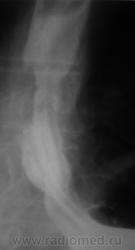

Пациент направлен на рентгенологическое исследование пищевода после ФГДС с диагнозом - "Пищевод Барретта".

Пациент первично был направлен в онкологический диспансер (областной). От туда он был направлен по месту жительства для производства ФГДС, которая и была проведена, был выставлен выше указанный диагноз.

После ФГДС, врач эндоскопист рекомендовал провести рентгеновское исследование пищевода.

1. Пищеводно-желудочный переход отсутствует - это одно из подтверждений пищевода Баррета.

2. Наблюдаемое сужение может быть следствием эзофагеального стеноза в зоне трансформации эпителия - это тоже подтверждение пищевода Баретта, но как без биопсии дифференцировать с инфильтративной формой рака....

3. Нишеподобное выпячивание по левой стенке может быть пептической язвой - это тоже характерно для пищевода Баретта....

4. Изменения в кардиальном отделе желудка по медиальной стенке - интересное и непонятное явление...думаю без биопсии тут никто не разберется, это и отек слизистой, это и рост в просвет...

Вывод, столь серьезная заявка, как пищевод Баретта, тем более с учетом возможности развития на этом фоне опухолевого поражения, требует ОБЯЗАТЕЛЬНОГО гистологического подтверждения....без биопсии НИКУДА....увы...

Циркулярное сужение в н/3 + отсутствие складок на уровне поражения + формирующееся престенотическое расширение = рак н/3 пищевода. Ну, а Барреты? А Барреты потом...